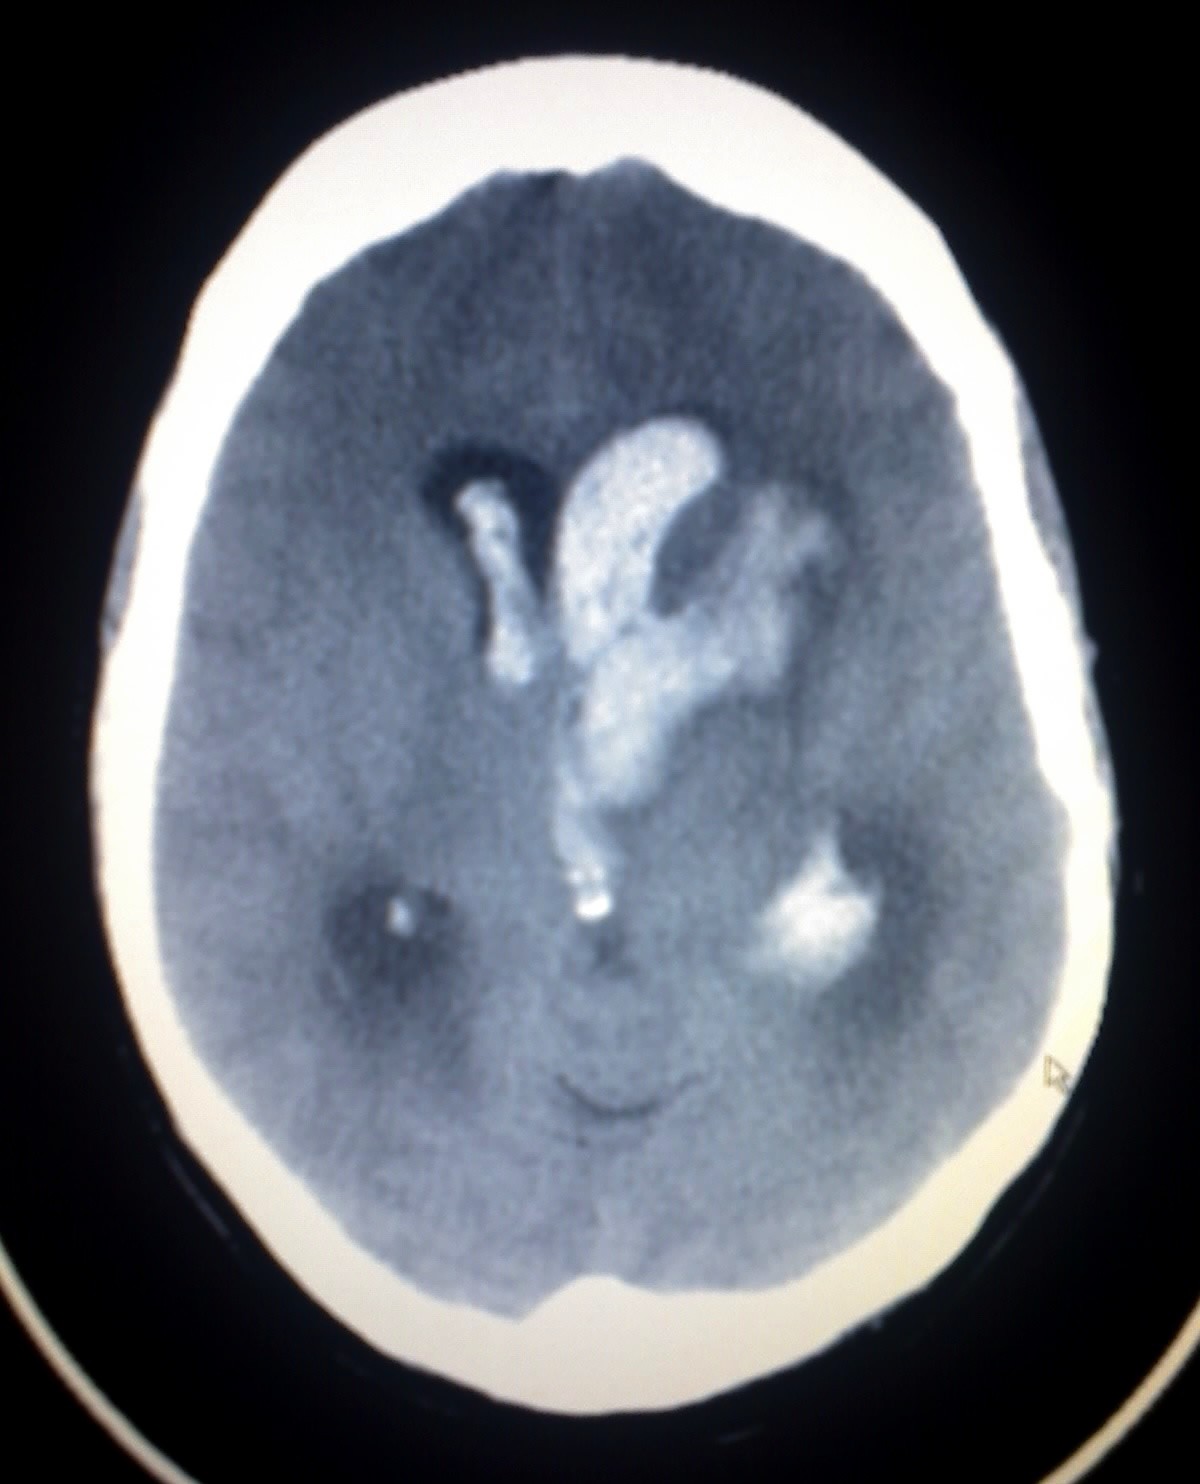

yüksek kan basıncı doğuştan anormal iner gibi nedenlerle beyin kan akımını sağlayan damarların yırtılması sonucu beyin dokusu içine kanama olması durumudur.

bir kan damarının beyinde patlamasıdır. kan pıhtılaşması, arterlerin (atardamarların) kalınlaşması ile birlikte olan yüksek kan basıncı, alkol veya kurşun ile olan kronik zehirlenmeler gibi etmenler buna sebeb olabilmektedir.

kısa sürede çok fazla tuz tüketmek beyin kanamasına yol açabilir. hipertansiyon, kan sulandirici ilaç kullanımlarına bağlı olarak da gelişebilir.

şiddetli bulantı kusma , konuşma ve hareket güçlüğü , görme kaybı gibi belirtileri vardır.